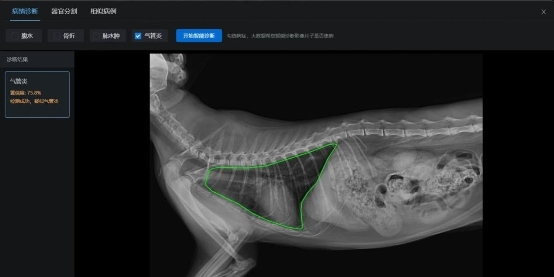

考虑到判断气管炎需要医生多年的专业知识的积累和高度集中的注意力来完成,谛宝诚将气管炎判断转化为分类任务,为每个图像分配一个标签,使用深度卷积神经网络来实现AI辅助系统,实现DR影像的疾病自动分析。其中,谛宝诚的AI辅助气管炎诊断系统就通过两阶段算法来实现。第一阶段,系统通过高精度器官分割模型确定胸腔区域,然后对胸腔区域裁剪;第二阶段,系统将裁剪图像送入分类模型进行气管炎分类。

由于系统的分割模型基于HRNet并加入自注意力机制,对胸腔区域实现高精度定位分类模型使用自研网络结构。针对胸腔x光图像分辨率高,同时医疗影像中细小特征较多、容易在小分辨率特征图上不可见的特点,谛宝诚科研团队还专门设计了高分辨率的骨干网络。模型使用海量宠物专家判读的气管炎影像数据进行训练,气管炎判断准确率在验证集为94.5%,测试集达到85%!